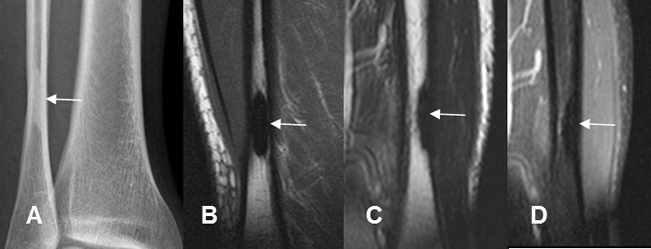

Fig 97 B. Defecto fibroso cortical.

A: Rx AP. Imagen densa, en la parte distal del peroné.

B: RM coronal en T1, C: RM sagital en T2 y D: RM sagital en STIR. Esta lesión es hipointensa en todas las secuencias y corresponde a la calcificación de un defecto fibroso cortical.